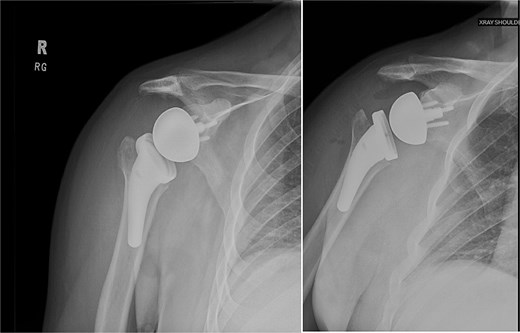

At 2 years after the initial injury, he continued to have right shoulder dysfunction, with forward flexion limited to 120°, external rotation limited to 30° with his arm at his side, and notable weakness with resisted external rotation at 4/5 strength despite injections, physical therapy, and arthroscopic debridement. Ultimately, he underwent rTSA with concurrent latissimus dorsi tendon transfer to address external rotation deficits associated with his posterior cuff deficiency. The subscapularis was additionally repaired using a medialized transosseous construct. He was maintained in an immobilizer for 6 weeks and then started formal therapy (Fig. 9).

Right reverse total shoulder arthroplasty at 3-month postoperative follow-up.